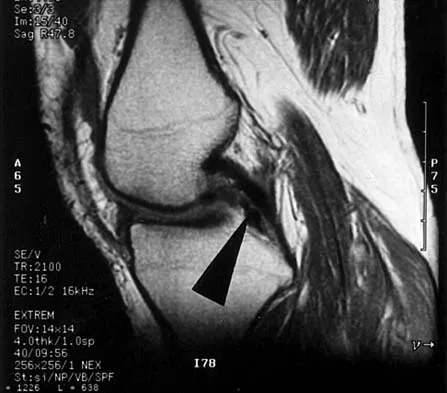

Figure 22 shows the MRI scan of a 20-year-old female basketball player who has pain over the anterior knee that interferes with her performance. Examination reveals phase III Blazina patellar tendinosis. Management should consist of

Explanation

Excision of the affected mucoid degenerative area is considered appropriate management in the Blazina classification system. A finding of phase III indicates persistent pain with or without activities, as well as deterioration of performance. With the appearance of the mucoid degeneration and the vigorous activity level of the intercollegiate basketball player, it is unlikely that nonsurgical management will provide adequate relief. When excising the affected degenerative area, care must be taken to retain normal tendon fibers. The defect in the patellar tendon is closed with absorbable sutures, as is the paratenon. Postoperative rehabilitation involves initial mobilization extension, with progressive range-of-motion and mobilization exercises as tolerated and weight bearing as tolerated. Open chain and isokinetic exercises are delayed until full range of motion and mobility is obtained, generally within 4 weeks. A return to activities is achieved by 80% to 90% of athletes, although there may be occasional activity-related aching for 4 to 6 months after surgery. Blazina ME, et al: Jumper's knee. Orthop Clin North Am 1973;4:665. Kelly DW, Carter VS, Jobe FW, Kerlan RK: Patellar and quadriceps tendon ruptures: Jumper's knee. Am J Sports Med 1984;12:375-380. Krums PE, Ryder B: Operative treatment of patella tendon disorders. Operative Techniques Sports Med 1994;2:303.